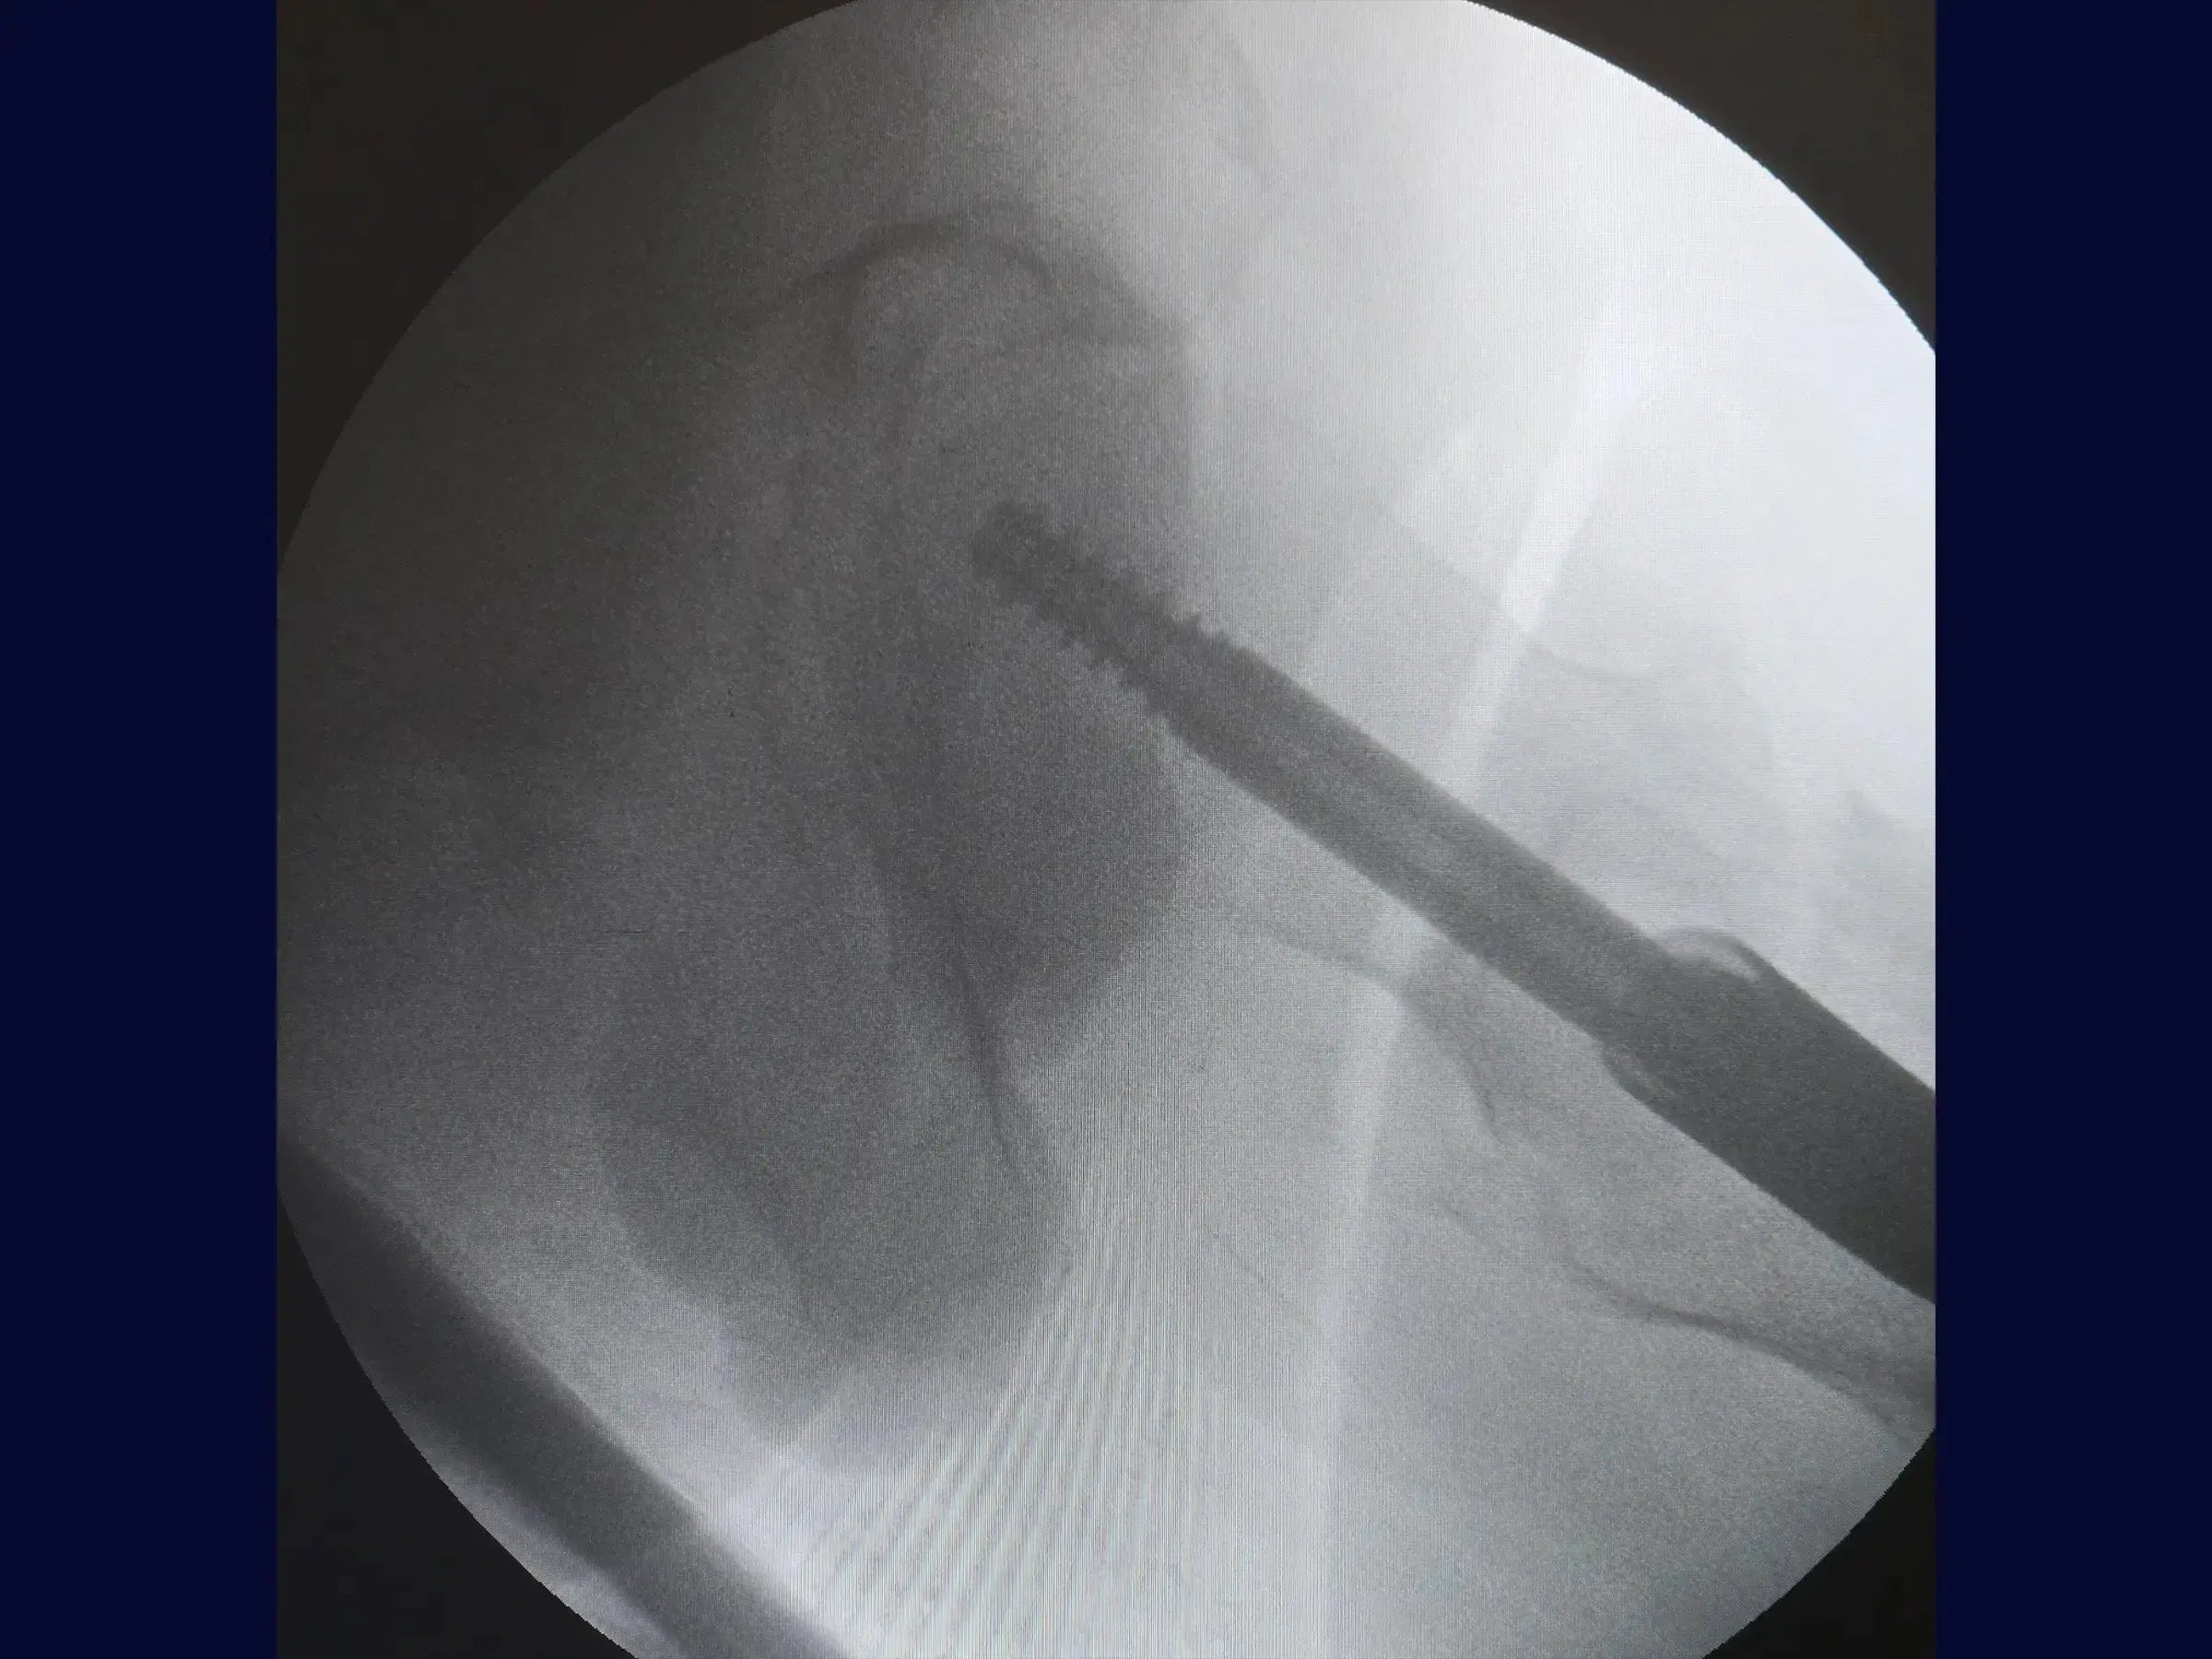

- Otimização Lateral e Haste: Para corrigir o posicionamento lateral do fio , use um guia de paralelismo que centraliza o fio no canal medular e colo femoral , evitando obliquidade do parafuso deslizante. Abra o canal medular com broca e protetor de partes moles, e introduza a haste intramedular curta.

- Inserção de Parafusos: Faça uma abertura minimamente invasiva lateral para o fio guia do parafuso deslizante, confirmando seu direcionamento para o centro da cabeça do fêmur em ambas as vistas. Meça e insira o parafuso deslizante, usando um segundo fio guia para evitar seu retorno. O bloqueio distal é guiado pelo introdutor da haste, com incisão de 1.5 cm. Certifique-se de que o parafuso deslizante permita pistonamento.